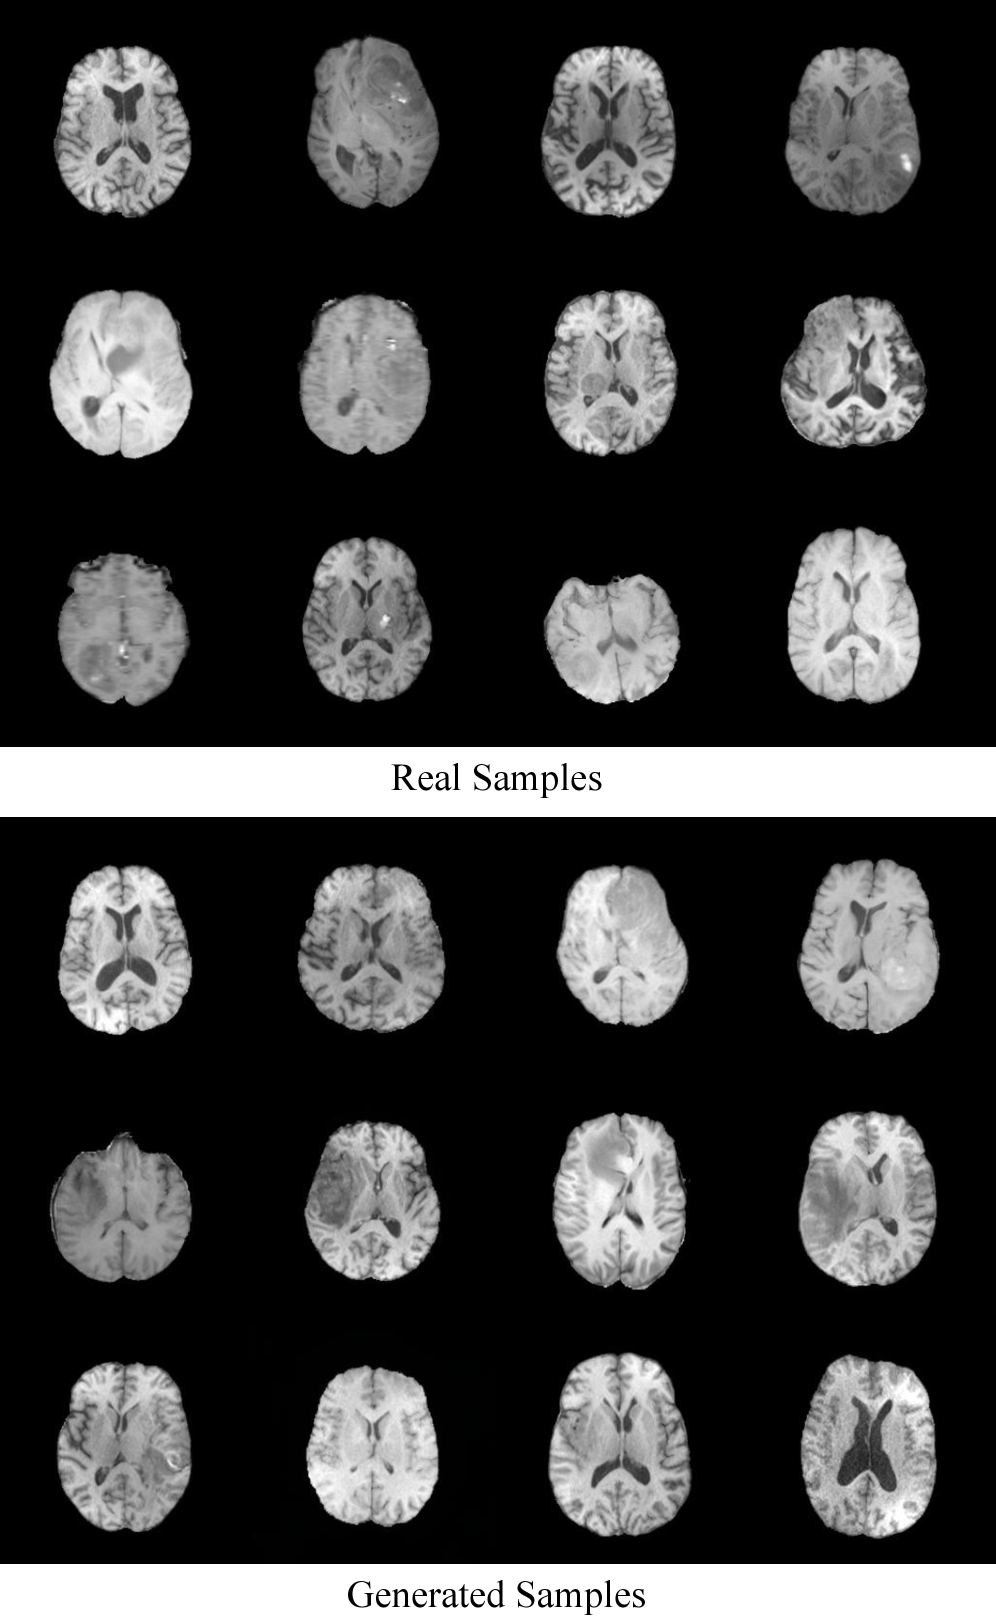

Refer to caption

Figure 9: Qualitative results on BraTS2021 T1 contrast. Top: real training samples. Bottom: images generated by HP-GAN fine-tuned from FFHQ, demonstrating successful transfer from natural to medical images.

As shown in Tab. 9, fine-tuning from FFHQ leads to a improvement in FID compared to training from scratch, indicating that HP-GAN benefits from natural-image pretraining even when the target domain is medical imagery. Fig. 9 provides qualitative examples for the fine-tuned model.